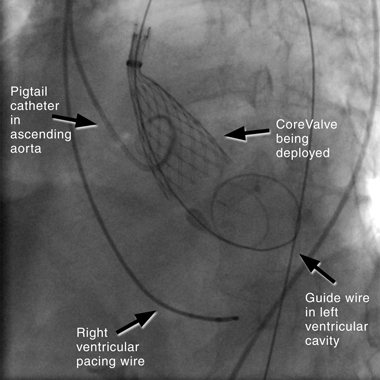

The retrograde approach has undergone rapid modification in recent years, due to the development of specialised closure devices that have allowed for a percutaneous procedure without the need for formal femoral surgical repair.16 It is now by far the most common approach to PAVR, because it is a simpler technique and has procedural similarities to coronary angiography. The technique (illustrated in Box 4) involves inserting a large sheath (18–22F) into the femoral artery, with a pre-closure device. If the subclavian route is used, a surgical cutdown is required, with direct suture closure of the vessel at the completion of the procedure. A right ventricular pacing wire is placed for rapid pacing (220 beats/min) that is performed during BAV and for temporary cardiac pacing if bradycardia occurs. The aortic valve is crossed using a guide wire, and the device is positioned across the valve. The CoreValve is self-deployed, and the Edwards SAPIEN valve is balloon-deployed under rapid ventricular pacing to reduce left ventricular stroke volume and reduce risk of device migration. The large femoral sheath is removed using the pre-closure device.

4 Fluoroscopic image in anterior–posterior projection showing retrograde deployment of CoreValve ReValving System